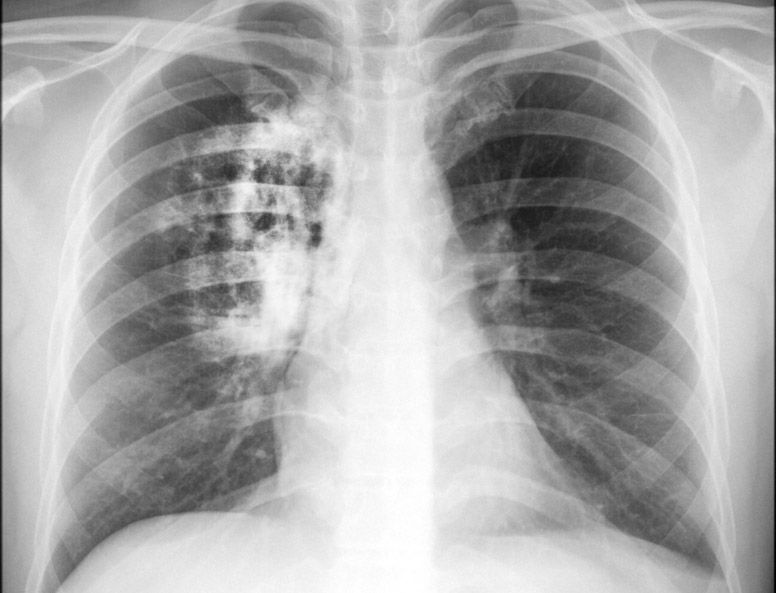

Que o câncer de pulmão não é uma doença assintomática?

Os sintomas mais comuns do câncer de pulmão são a tosse, falta de ar e o sangramento pelas vias respiratórias. Nos fumantes, o ritmo habitual da tosse é alterado e aparecem crises em horários incomuns para o paciente. Pneumonia de repetição pode, também, ser a manifestação inicial da doença. Fique atento aos sintomas.

Que existe mais de um tipo de câncer de pulmão?

O câncer de pulmão é classificado em dois tipos principais: pequenas células (15%) e não-pequenas células (85%). O tumor de não-pequenas células corresponde a um grupo heterogêneo composto de quatro tipos histológicos principais e distintos: carcinoma epidermóide, adenocarcinoma,  carcinoma de grandes células e carcinoma bronquíolo-alveolar (que muitas vezes é uma variante do adenocarcinoma).  Um dos tipos de câncer de pulmão é causado por uma mutação no gene EGFR e para isso já existe um tratamento especifico denominado “alvo molecular”, com drogas orais (como a Gefitinibe e o Erlotinibe, usados no tratamento de câncer de pulmão de não pequenas células).